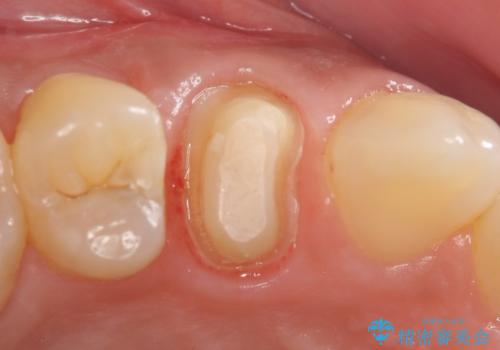

- 右上の歯茎の腫れが引かないので診て欲しいといらっしゃった方の症例です。

検査の結果、右上4番目の歯は神経が死んでおり、そのせいで歯茎に膿の出口が出来ていることがわかりました。

右上4は根管治療を行い、オールセラミッククラウンによる補綴を行いました。